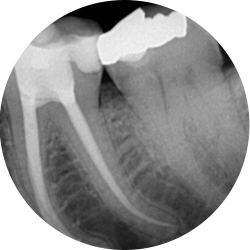

Bacteria associated with decay, deep restorations, fractures, trauma or periodontal disease may irreversibly damage the pulp. In order to preserve a tooth, in which this has occurred, it is necessary to remove the injured, infected tissue. This procedure is known as root canal therapy.

Most endodontically treated posterior teeth require restoration with a crown on completion of treatment. In some instances crown placement is delayed to assess the success of the endodontic treatment. Covering the tooth with a cast restoration significantly increases its long term survival.

If the tooth is already restored with a crown prior to treatment then it maybe possible to treat the tooth through the existing restoration.